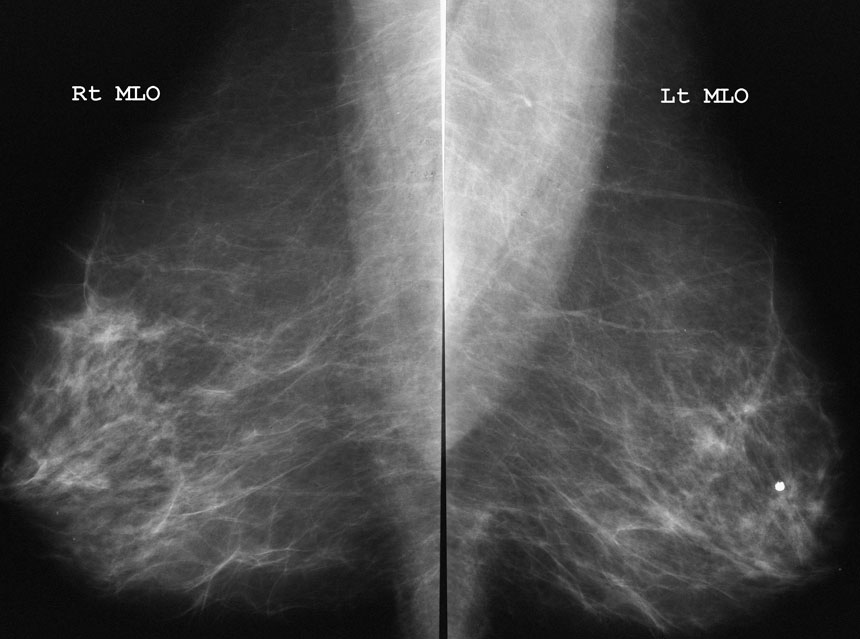

Mammography (Breast Imaging)

Breast imaging uses x-ray and ultrasound to examine the breast. The most common tests that we carry out are mammography, ultrasound and biopsy.

A mammogram is an x-ray picture of the breast. It is used to detect and diagnose breast disease in women who either have breast problems such as a lump, pain, or nipple discharge, as well as for women who have no breast complaints. The procedure allows detection of breast cancers, benign tumours and cysts before they can be felt.

Mammography cannot prove that an abnormal area is cancerous, but if it raises a significant suspicion, a biopsy may be performed.